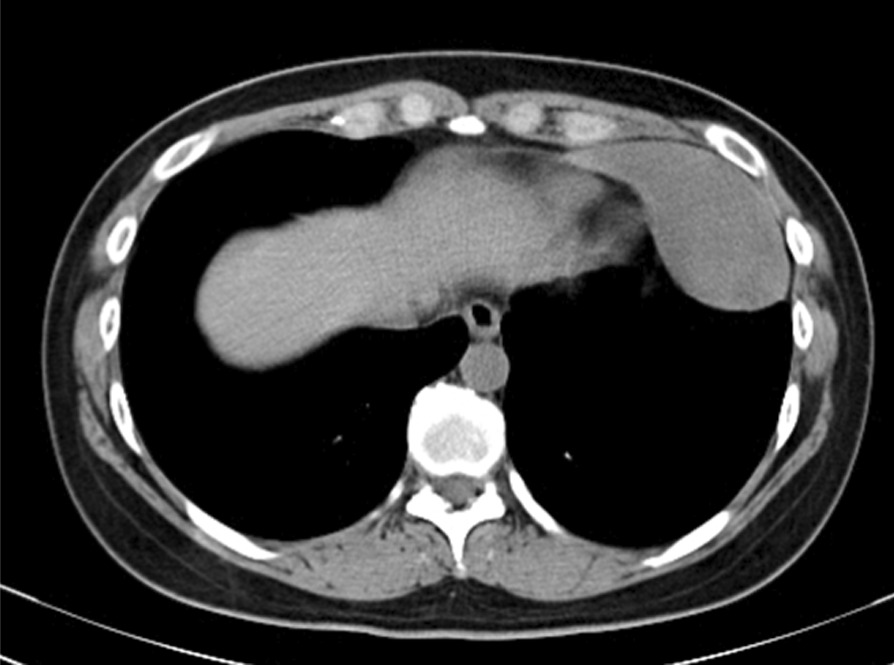

A 32-year-old Asian female visited us for examination of an abnormality on her chest X-ray. There was a well-defined mass lesion around the apex of the heart. The mass had developed and grown within 1 year (Fig. 1A, B). The tumor size enlarged from 34 to 64 mm in the largest diameter by chest X-ray. The patient was asymptomatic, had never smoked, and had a history of hyperthyroidism treated with thiamazole. However, she was medication-free on admission to our hospital. She had no history of pregnancy and no history of childbirth. There was no remarkable family history of illness, including cancer. She is a desk worker with no history of exposure to certain chemicals or asbestos. Her vital signs, physical examination, and neurological examination on admission were unremarkable. Her laboratory finding was within the standard limit on blood cell counts, liver and renal functions, urinalysis, and other serology. Chest computed tomography (CT) revealed a pear-shaped mass lesion measuring 80 mm in the largest diameter that had developed between the pericardium and the left lung (Fig. 2). The lesion was monotonous and had a computed tomography value between 23 and 32 HU. It was growing expansively and did not seem to invade the adjacent organs. The lesion showed a low signal on T1-weighted magnetic resonance imaging (MRI) and a low and heterogeneous signal on T2-weighted fat-saturation imaging (Fig. 3A, B).

Fig. 2.

Chest computed tomography image of the tumor. The tumor was located on the pericardium and did not seem to invade the adjacent organs. The tumor had a pedicle on the pericardium

The preoperative diagnosis was difficult. Computed tomography showed a uniform tumor connected to the pericardium. The computed tomography value of the tumor and the MRI findings excluded the probability of cystic disease. Imaging differential diagnosis included diverse kinds of soft-tissue tumors and thymic epithelial tumors. However, the pear shape of the tumor is not typical of thymoma. Both CT and MRI showed no fat component inside the tumor, so lipoma and liposarcoma were ruled out. Due to the rarity of soft-tissue tumors of the mediastinum, further diagnosis by imaging alone was difficult.